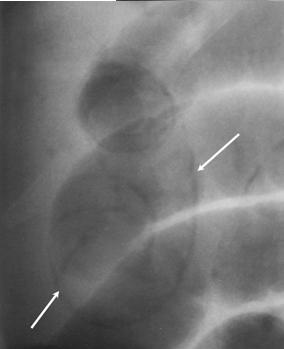

Complication de pneumatosis du

colon parfois se presente : Image de couche de air

intra -parietale du colon ( fleche blanche ) . |

Complication de perfore et

peritonite dans les cas graves parfois se presentent

. Image de croisante gaseuse sous diapragmatique

droit d'une colite ischemique perfore |